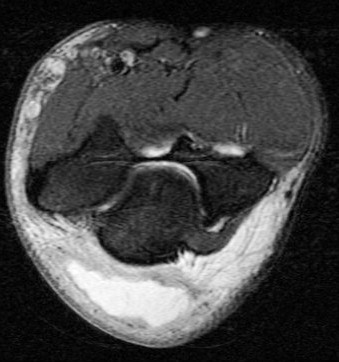

Figure 1 for case olecranon bursitis ( RID2082 )

Figure 1

Fluid and bursal lining thickening. Area edema. This was non septic. No osteomyelitis. Reference article.

olecranon bursitis ( RID2082 )